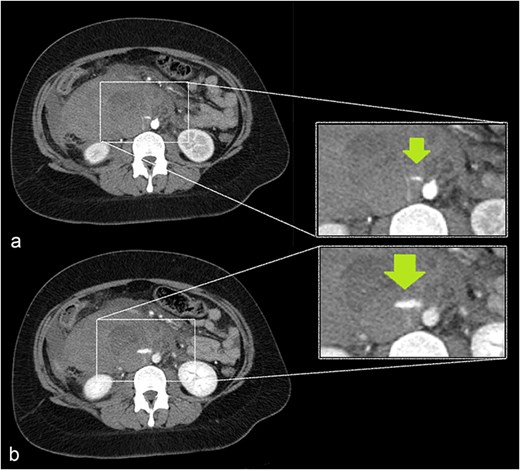

Sagittal plane CECT shows the hematoma (H) displacing the pancreas ventrally, proving its retroperitoneal location. Active bleeding is seen adjacent to the gestational sac (arrow). A normal appearing, nonpregnant uterus is also visible.

Our patient had an uneventful vaginal delivery, no abortions, no curettages, or tubal sterility. The patient’s only relevant history was of abdominal trauma during a traffic accident. A study by Cigerci et al found abdominal injuries to be present in as many as 23% of patients with traumatic thoracolumbar fractures [12]. The position of the gestational sac is just below the level of the fractured L1 vertebra (Fig. 7) could suggest an association of RPEP with previous abdominal trauma.

CECT of the abdomen and pelvis in the sagittal plane, bone window. Gestational sac (H for hematoma) was implanted just inferior to the level of a previous traumatic L1 vertebral fracture (arrow).